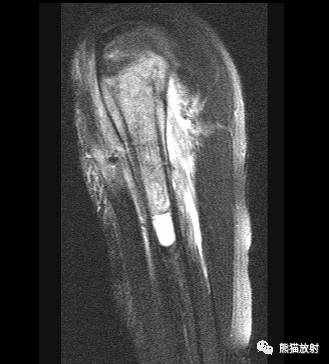

II型及III型 ↓ 肱骨上段Ewing肉瘤(男7岁)

↓ 肱骨上段纤维结构不良并病理性骨折(男23岁)